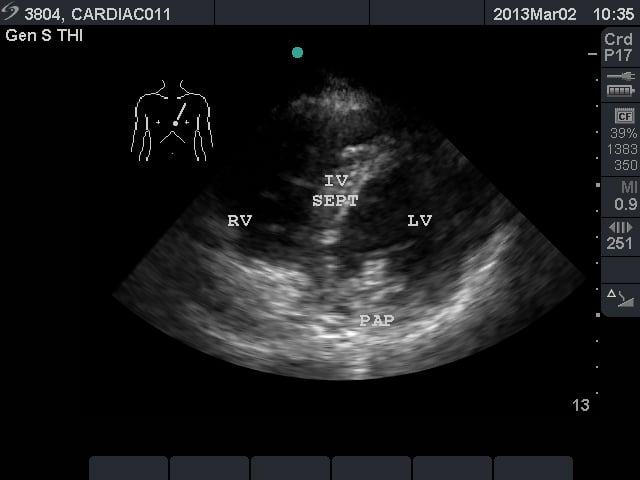

Video 2. Normal parasternal long axis view - Parasternal Short Axis View: This view is a cross sectional view of the left and right sides of the heart. These can be “sliced” at various levels between the base and the apex. By fanning the probe towards the right shoulder, one can visualize the aortic valve in cross section. The “Mercedes Benz” sign shows all three of the leaflets. The right ventricular outflow tract and pulmonary valve can be seen in this view. At the base, the mitral valve is seen inside the left ventricle. At the mid ventricular level, the papillary muscles are seen within the left ventricle. This is the most commonly used parasternal short axis view in point-of-care ultrasound in the acute care setting. At the apex, the left ventricle has tapered and no structures are seen within.

- Figure 3. Parasternal short axis view at the mid ventricular level. RV = right ventricle. IV SEPT = interventricular septum